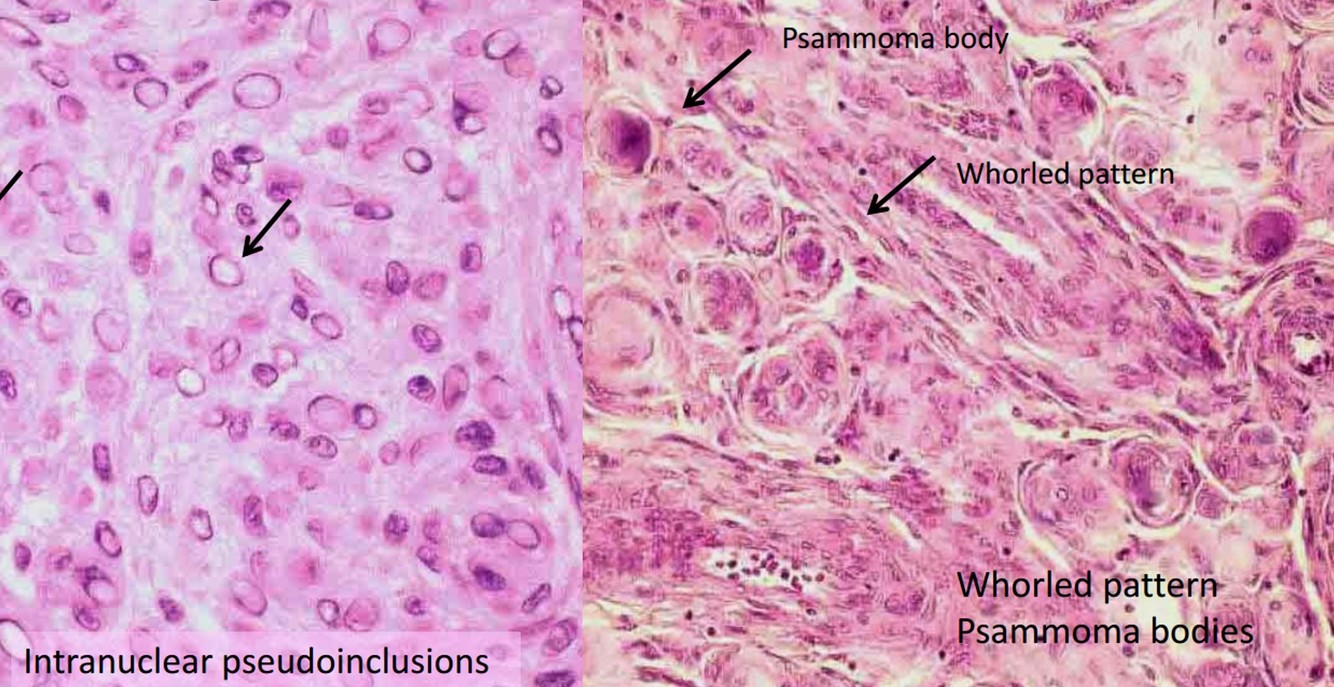

Meningioma Grades and subtypes

Meningioma Grades and subtypes

- Grade I (92%): most common, “cure” possible with complete resection

- Meningothelial, fibrous, transitional, psammomatous, angiomatous, microcystic, secretory, lymphoplasmacyte-rich, mataplastic

- Grade II (7%): higher rate of recurrence

- Atypical, clear cell, chordoid

- Grade III (rare): highly aggressive

- Anaplastic, rhabdoid, papillary